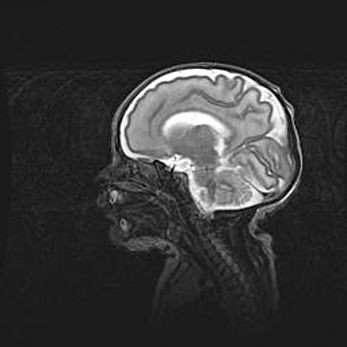

Наружная гидроцефалия с возможной атрофией височных областей.

Возраст: 28 дней

Вес: 3670 г

Пол: мужской

Окружность головы: 38 см

Срок гестации: 40 недель

Гидроцефалия головного мозга у новорожденных – это заболевание, которое характеризуется скоплением избыточного количества спинномозговой жидкости в желудочковой системе головного мозга в результате затруднения её перемещения от места выработки к месту поглощения в кровеносную систему или вследствие нарушения абсорбции. При открытой наружной форме гидроцефалии у новорожденных расширяются и переполняются субарахноидные пространства.

При нормотензивных  формах,  которые,  как  правило,  являются  следствием  перенесенных ишемических  повреждений  паренхимы  мозга,  возможно  сочетание микроцефалии  с нормотензивной гидроцефалией. В основе данных изменений лежит атрофия больших полушарий с преимущественной  локализацией  в  лобно-височных  областях.